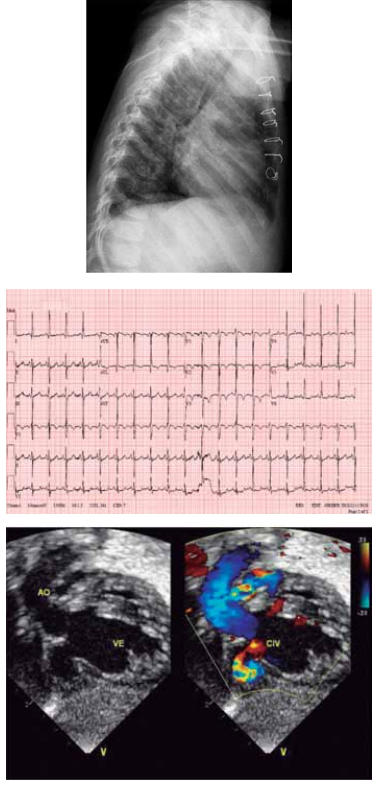

Considere as imagens a seguir.

(Arquivo pessoal; imagens usadas com autorização)

Qual é o diagnóstico provável da cardiopatia congênita ilustrada pela radiografia de tórax e a figura de ecocardiograma apresentadas desse recém-nascido?